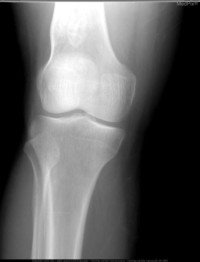

接下来使用下面三张图片进行接口测试:

分类预测:

$ img1=$(base64 -i ultrasound.jpg | tr -d '\n')

$ img2=$(base64 -i computed-tomography.jpg | tr -d '\n')

$ img3=$(base64 -i x-ray.jpg | tr -d '\n')

格式化后响应如下,第一张图片约 98% 概率为超声,第二章图片约 92% 概率为 CT,第三章图片约 99% 概率为 X 光:

{

"Clinical Photography": 0.0005790339782834053,

"Computed Tomography": 9.118935122387484e-05,

"Dermoscopy": 4.344608441897435e-06,

"Magnetic Resonance Imaging": 5.670949030900374e-05,

"Optical Coherence Tomography": 5.706364390789531e-05,

"Ultrasound": 3.7378162232926115e-05,

"X-Ray": 0.9991742968559265

}